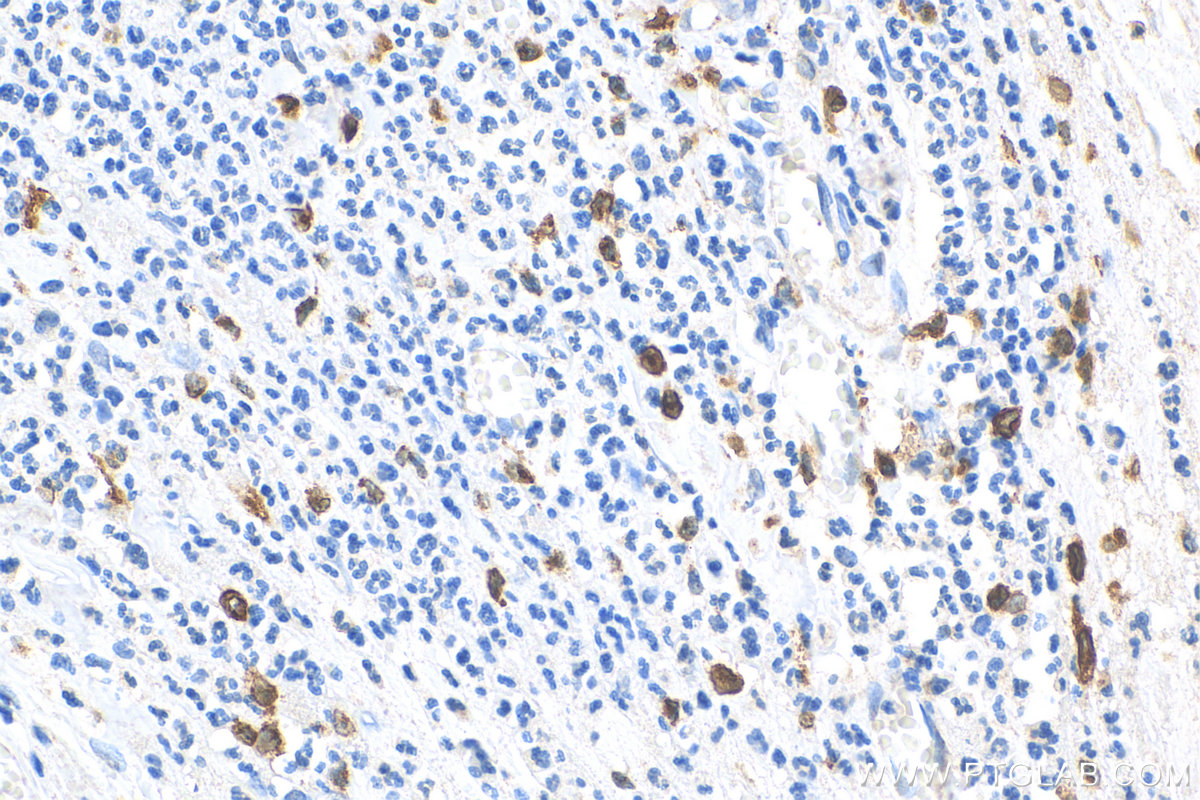

| Positive IHC detected in | human liver tissue, human appendicitis tissue, human lung cancer tissue, human placenta tissue, human tonsillitis tissue Note: suggested antigen retrieval with TE buffer pH 9.0; (*) Alternatively, antigen retrieval may be performed with citrate buffer pH 6.0 |

| Immunohistochemistry (IHC) | IHC : 1:2500-1:10000 |

CD163 is a transmembrane protein which belongs to the scavenger receptor cysteine-rich (SRCR) superfamily. This protein is a scavenger receptor for the hemoglobin-haptoglobin complex and is a marker for monocytes and macrophages. Soluble CD163 (sCD163), as a result of ectodomain shedding during inflammatory activation of macrophages, circulates in blood and has been suggested as a plasma/serum marker for macrophage activity.